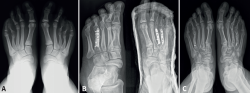

Figura 2. Paciente de 13 años con braquimetatarsia múltiple bilateral. A: radiografía simple en proyección dorsoplantar en carga previa a la cirugía donde se aprecia acortamiento congénito del cuarto metatarsiano del pie izquierdo y de los metatarsianos tercero y cuarto del pie derecho; B: radiografía simple en proyección dorsoplantar tras cirugía de alargamiento agudo con injerto autólogo de peroné y fijación con placas bloqueadas. Se observa zona de retardo de la consolidación en el pie izquierdo; C: radiografía simple en proyección dorsoplantar tras la retirada de las placas al año de la cirugía.